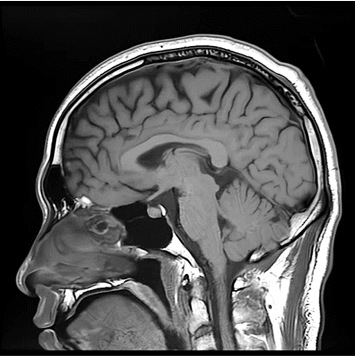

향상된 영상화질

향상된 대조도

노이즈 개선

모든 해부학적 부위 적용가능

Conventional

384 x 256 (4 NEX)

3:00 minIAI (Innovative AI)

384 x 256 (2 NEX)

1:29 minscan time reduced up to 50%

IAI는 AI Deep learning을 통해 기존 장비의 촬영 프로토콜을 최적화합니다.

기존 프로토콜 대비 촬영 시간을 50% 단축시키며, 이미지 퀄리티는 증가합니다.